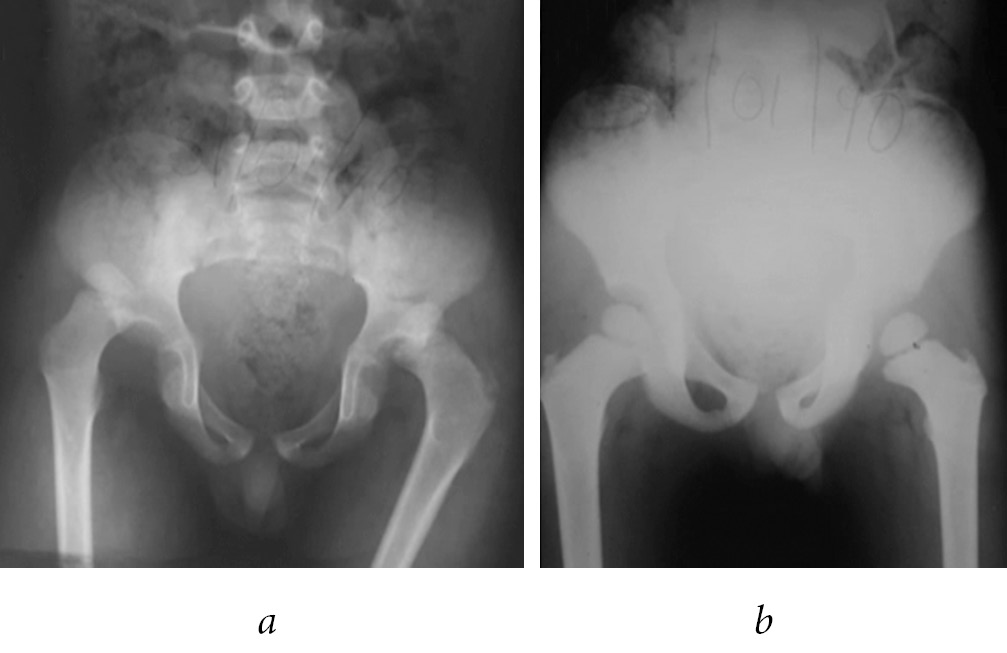

After 12 months, he was asymptomatic, without limitation of mobility arcs, performing daily activities and play without limitations (Fig. 2).

Fig. 2. Pelvis X-ray after 12 months of follow up (a); last X-ray control. Pelvis after 12 years of follow up with skeletal maturity achieved (b)

On follow-up of 12 years after the injury, at the age of 16 years-old presented independent march, without limping; full mobility arcs, a pelvic radiography was obtained and did not revealed any abnormalities.